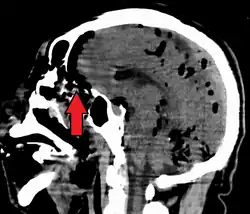

| Pneumocephalus and comminuted fracture of the frontal sinus |

Pneumocephalus is the presence of air or gas within the cranial cavity. It is usually associated with disruption of the skull: after head and facial trauma, tumors of the skull base, after neurosurgery or otorhinolaryngology, and rarely, spontaneously. Pneumocephalus can occur in scuba diving, but is very rare in this context.

CT scans of patients with a tension pneumocephalus typically show air that compresses the frontal lobes of the brain, which results in a tented appearance of the brain in the skull known as the Mount Fuji sign.[1][2][3] The name is derived from the resemblance of the brain to Mount Fuji in Japan, a volcano known for its symmetrical cone. In typical cases, there is a symmetrical depression near the midline (such as the crater of a volcano), due to intact bridging veins.[3] Its occurrence seems to be limited to tension pneumocephalus (not occurring in pneumocephalus without tension).[4] The sign was first described by a team of Japanese neurosurgeons.[5]